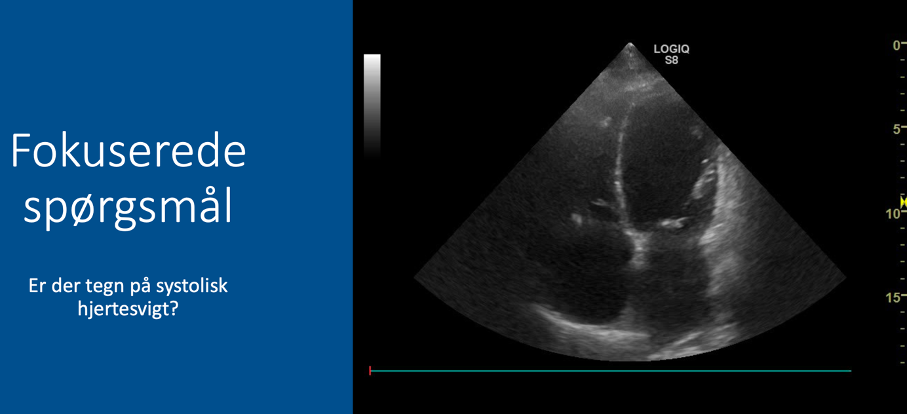

Fokuserede spørgsmål (FHUS):

* Tegn på systolisk hjertesvigt: ja/nej?

Kommer vægstrukturerne (hjertets vægge) mod midten i systolen?

* Hvis JA (væggene bevæger sig mod midten): IKKE tegn på systolisk hjertesvigt

* Hvis NEJ (væggene bevæger sig ikke ind mod midten, eller bevægelsen er sløv): tegn på systolisk hjertesvigt / nedsat EF (ejektionsfraktion)